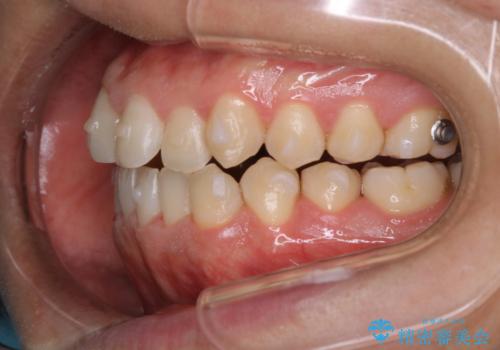

インビザラインでの矯正治療は、歯の表面にアタッチメントといって白い突起を付けますので、材料の質的にも普段よりも汚れがかなり付着します。着色も付きやすいです。

虫歯や歯周病が進行しないように定期的にクリーニングすることをおすすめします。インビザライン経過のチェックが2、3ヶ月に1回のためそのくらいのペースで一緒にクリーニング行うことが最適です。